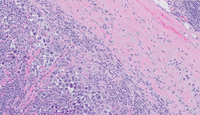

Figure 2: H&E High Power in Extracavitary Primary Effusion Lymphoma

The image on the top left shows capsular sclerosis with subcapsular, sinusoidal infiltrate of discohesive atypical cells within the subcapsular sinus and trabecular sinuses.  The image on the top right depicts reactive secondary lymphoid follicles on the right side with prominent mantle cuffs and adjoining area to the left of it showing clusters of large atypical cells within the sinuses.

The image at the bottom left shows the large atypical cellular clusters within the sinusoids in the parafollicular areas exhibiting anaplastic and plasmablastic/plasmacytic cytomorphology with abundant cytoplasm and variably prominent nucleoli.

There are multifocal collections of these cells throughout the lymph node located exclusively within the subcapsular and interfollicular sinusoidal regions.